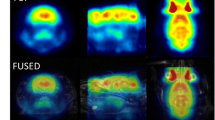

Supplementary Fig. 1 Co-registration of microPET and MRI images. 6 of 17 slices of coronal views of the rat brains are displayed. The regions of interest (ROIs) are drawn according to the anatomical structures and are numbered. The ROIs correspond to the following brain regions: 1 prefrontal cortex, 2 sensorimotor cortex, 3 striatum, 4 piriform cortex, 5 hippocampus, 6 amygdala, 7 thalamus, 8 visual cortex, 9 auditory cortex, 10 entorhinal cortex, 11 pons, 12 cerebellum (TIFF 6307 kb)